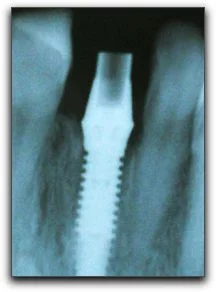

A Fresh Start After Losing A Tooth

Are you one of the many men and women who has had a tooth extracted? If the tooth had been bothering you, it may have